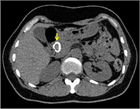

1. 膵管内の結石(膵石)を認めた場合と、膵全体に分布する複数かつびまん性の石灰化を認めた場合は慢性膵炎と診断できる(推奨度1)

1. 加齢現象に伴い膵石が観察される場合がある。

1. 石灰化を伴った膵腫瘍がまれに存在する。